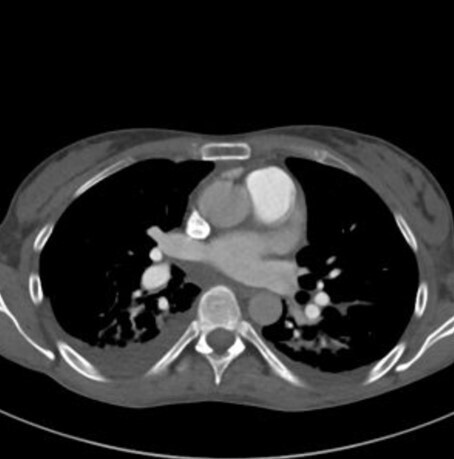

Lors de cette surveillance échographique, une image nodulaire du dôme hépatique apparaît. Le scanner ci-dessous est réalisé pour caractériser cette lésion.

Question 8 - Les caractéristiques sémiologiques de cette lésion sont :

La lésion est hypodense sans injection, mais de densité plus élevée que la graisse sous-cutanée qui apparait presque noire ici (NB : le CHC graisseux est une entité qui existe mais rare).

Le temps artériel se reconnait grâce à la densité importante des artères (par exemple l’aorte).

On parle d’hyperdensité en scanner et d’intensité en IRM.

Un envahissement tumoral vasculaire se manifesterait sous la forme d’une plage infiltrante hypervasculaire au temps artériel au sein de la veine.

Lésion nodulaire typique de carcinome hépatocellulaire (CHC) en scanner : nodule bien délimité hypodense sans injection, hypervasculaire au temps artériel (« wash-in »), présentant un lavage au temps portal et tardif (« wash-out »), et une capsule (dont la définition est la présence d’une couronne se rehaussant au temps tardif).

Un scanner réalisé pour caractérisation d’une lésion hépatique doit comprendre une phase sans injection, une phase artérielle, une portale et une tardive à 3 minutes. Un scanner thoracique pourra également être réalisé dans le bilan d’extension du CHC.

L’imagerie est donc évocatrice de carcinome hépatocellulaire (CHC).